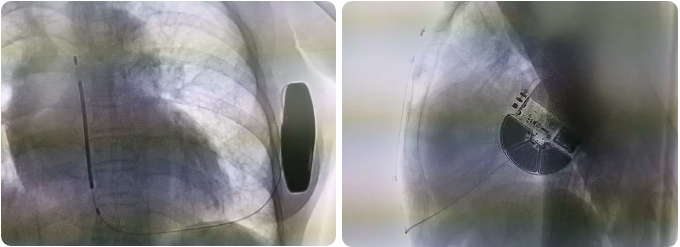

术后影像

术中行DFT测试,S-ICD正确识别室颤后成功除颤转复,除颤能量65焦耳,除颤阻抗56欧姆。手术圆满成功,耗时约1.5小时。